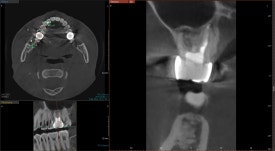

20240805

CT를 찍어보니 오른쪽 위 신경치료한 치아에서

염증이 발생한 것을 알 수 있었습니다.

치아 내부에 원인이 있는 경우,

염증은 대개 뿌리 끝에 동그랗게 잡히게 됩니다.

CT를 면밀히 분석한 결과,

이전에 받은 신경치료에서

놓친 부위가 있다는 것을

확인할 수 있었습니다.